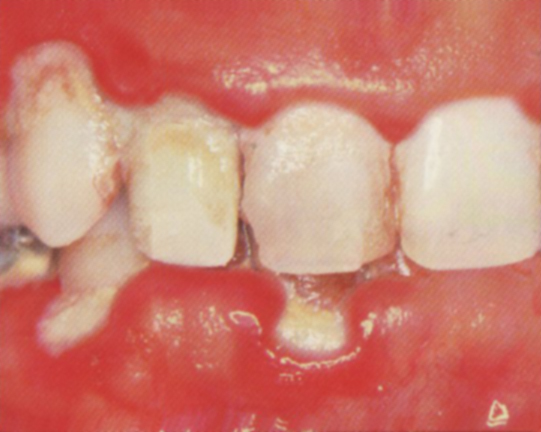

Střední parodontitis obr. 4

- dásně ustupují, odhalují se citlivé zubní krčky

- zuby vypadají delší

- zarudnutí, otok a krvácení dásní je výraznější

- dásně jsou citlivé až bolestivé

- zápach z úst, poruchy chuti

- sondovatelná hloubka dásňového žlábku se prohlubuje na 4-6 mm

- na rtg je patrný úbytek horizontální i vertikální úbytek kosti